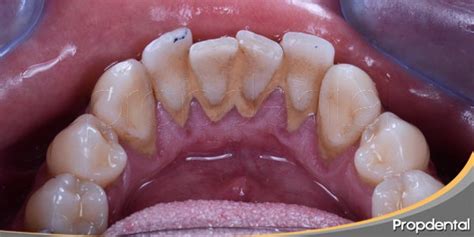

Lo primero es entender qué es exactamente el sarro. Básicamente, el sarro es una acumulación endurecida de placa bacteriana. Todos tenemos bacterias en la boca que, junto con los restos de comida que quedan después de comer, van formando una capa pegajosa llamada placa. Si no eliminamos esa placa a tiempo (con un buen cepillado y uso de hilo dental), se endurece y se convierte en sarro.

Normalmente, el sarro tiene un tono amarillento o marrón, pero en algunos casos, puede adquirir un color verde. ¿Por qué verde? Vamos a verlo en detalle:

A ver, el color verde puede parecer alarmante, pero el peligro no está en el color en sí. El verdadero problema es el sarro en general, sea del color que sea. ¿Por qué? Porque el sarro es como una capa dura que se adhiere a tus dientes y favorece la acumulación de bacterias. Si no se elimina, puede tener consecuencias bastante graves para tu salud bucodental.

Tener sarro verde en los dientes de abajo o arriba puede ser un indicador de que es momento de revisar tu higiene bucal y pedir cita con el dentista. No se trata solo de una cuestión estética, sino de prevenir problemas más serios como la gingivitis, la periodontitis o las caries. La buena noticia es que, con una limpieza profesional, puedes eliminarlo y evitar complicaciones futuras.